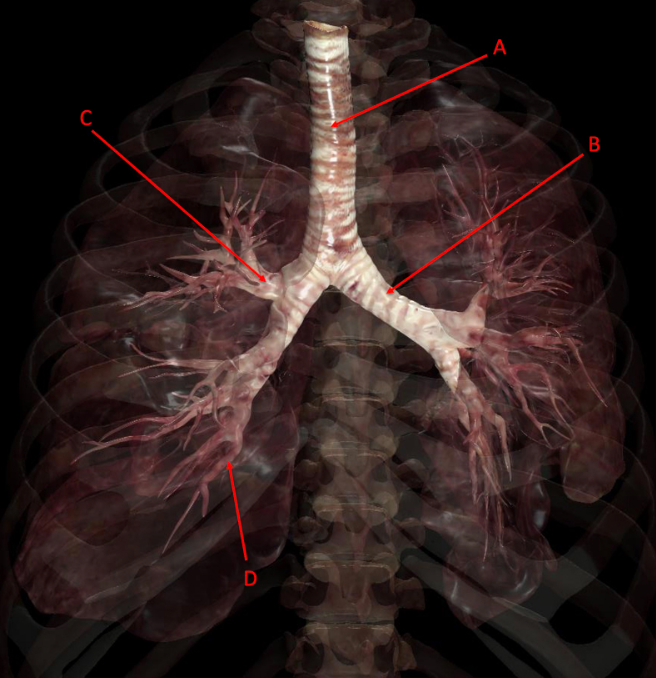

A

A. trachea

B. left main bronchus

C. Right superior lobar bronchus

D. segmental bronchus